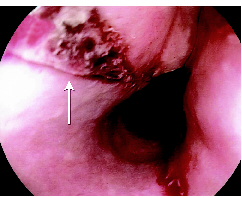

ard Roth Net retriever (US Endoscopy, Mentor, Ohio, USA) (a snare with a mesh basket) leaving a longitudinal mucosal tear (Box 2). There was no evidence of oesophageal perforation and she made a rapid and complete recovery, being discharged after 48 hours on pantoprazole in addition to her usual medications. At follow up after 2 weeks, she remained well and pantoprazole was ceased.